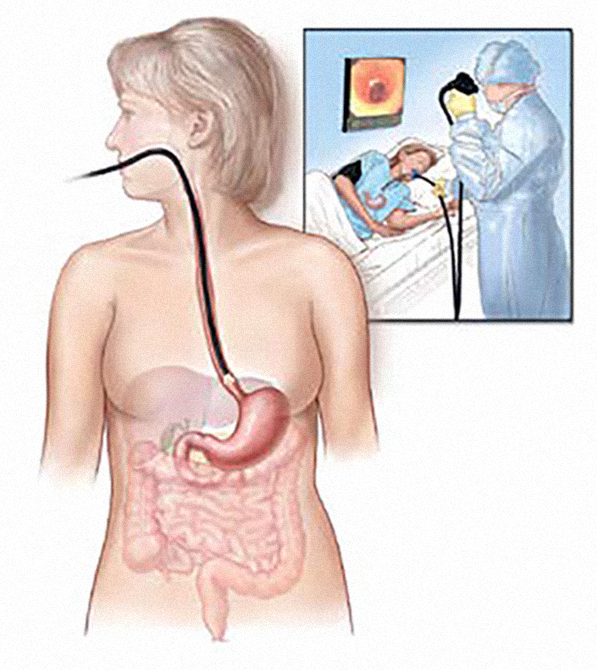

Gastroezofagealna refluksna bolest dijagnostikuje se gastroskopijom, odnosno gornjom fleksibilnom endoskopijom, koja omogućava detaljan uvid u stanje sluzokože gornjih digestivnih organa. Ova dijagnostička procedura, koja se još naziva i ezofagogastroduodenoskopija (EGDS), može da identifikuje eventualne promene na jednjaku, suženja jednjaka ili Baretov jednjak, kao i da pruži podatke o postojanju i veličini želudačne kile.

Endoskopija je vizuelna inspekcija unutrašnjosti šupljih telesnih organa uz pomoć fleksibilnog endoskopa, aparata opremljenog kamerom i svetlom, koji se u digestivni trakt uvodi kroz usnu duplju. Prof. Simić ističe da je endoskopija značajno proširila mogućnosti razumevanja mehanizama oboljenja jednjaka i želuca, te je ezofagogastroduodenoskopija (gastroskopija) danas najvažniji dijagnostički pregled kod sumnji na oboljenja gornjeg digestivnog trakta na osnovu koga sa sigurnošću može da se postavi dijagnoza i odredi adekvatna terapija. Naš sagovornik dodaje da svaki simptom koji ukazuje na oboljenje jednjaka ili želuca - gorušica, regurgitacija, otežano gutanje, bol iza grudne kosti nesrčanog porekla, gubitak apetita i telesne težine, bol u predelu želuca ili ispod rebarnog luka, nadimanje i otežano varenje, učestalo povraćanje, povraćanje krvi i pojava crne stolice, anemija nepoznatog razloga - a koji dugo traje, zahteva gastroskopiju čak i u slučajevima kad radiografski pregled nije ukazao na patološki nalaz.

Endoskopija |

Takođe, kod sumnje na GERB, veoma je dragocena a nekad i nepohodna dijagnostička procedura 24-časovna pH-metrija sa impedancom. Ona tokom 24 sata meri količinu želudačne kiseline koja se vraća iz želuca u jednjak, i tako obezbeđuje vrlo značajne podatke na osnovu kojih se, uz gastroskopski nalaz, pravi strategija i plan lečenja obolelog.